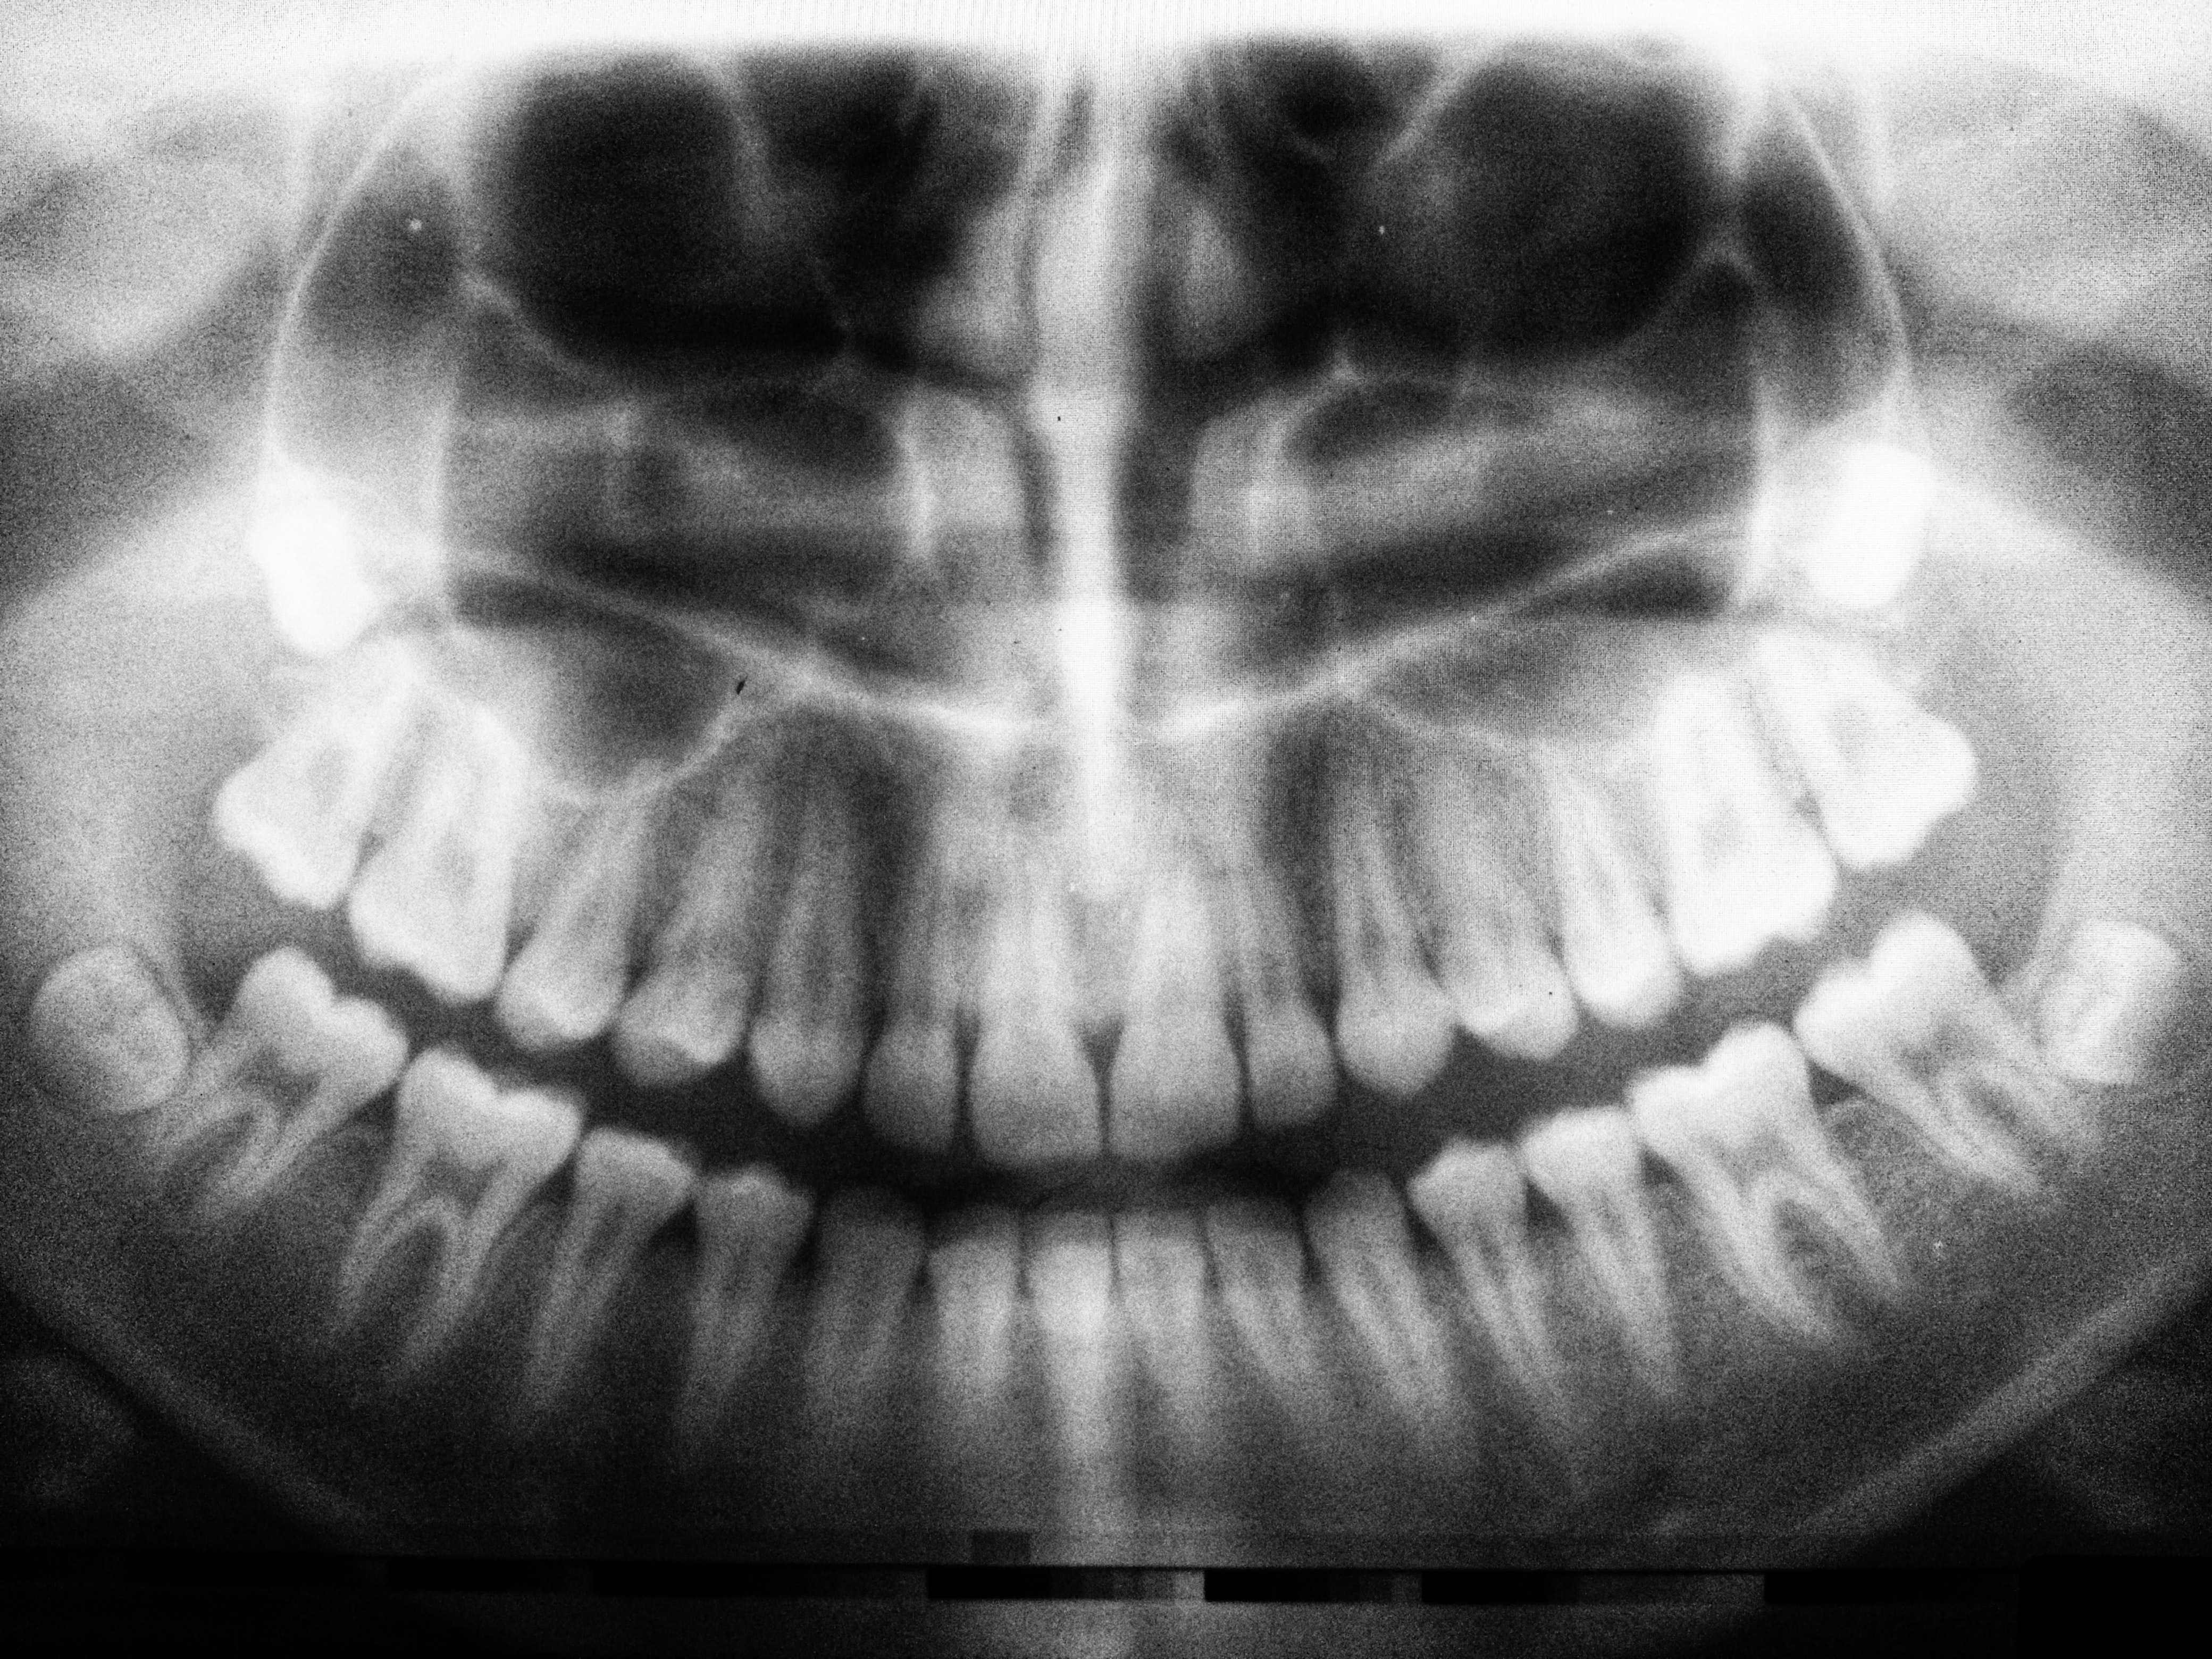

상실된 치아를 인공 치아의 이식을 통해 건강한 구강을 가지게 하는 의학의 한 분야입니다. 본래는 인체의 조직이 상실되었을 때 이를 회복시켜 주는 대치물을 의미하지만 치과에서는 인공 치아 이식을 말합니다.

치과임플란트 보험급여 대상은 만 65세 이상의 건강보험 가입자 또는 피부양 자로, 국민건강보험공단에 사전 등록 후 진료를 시작하는 경우에 대하여 보험 급여가 가능합니다. 보험급여가 되는 치과임플란트는 상악 또는 하악에 부분 무치악으로 악골 내에 분리형 식립재료(고정체, 지대주)를 사용하여 비귀금속도재관(PFM Crown)보철수 복을 실시하는 경우입니다.